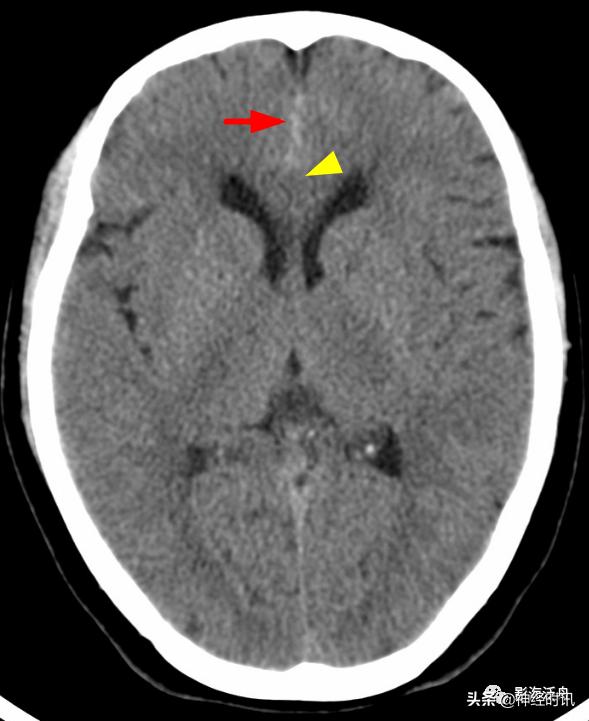

典型的大脑镰前部少量蛛血,血肿的边缘毛糙(红箭)且抵达胼胝体膝部的前缘(黄箭头)。4天后复查头颅CT平扫,相应部位少量蛛血基本吸收。

另一例表现类似的大脑镰前部少量蛛血,血肿的边缘总是有一种毛毛糙糙的感觉(红箭)。